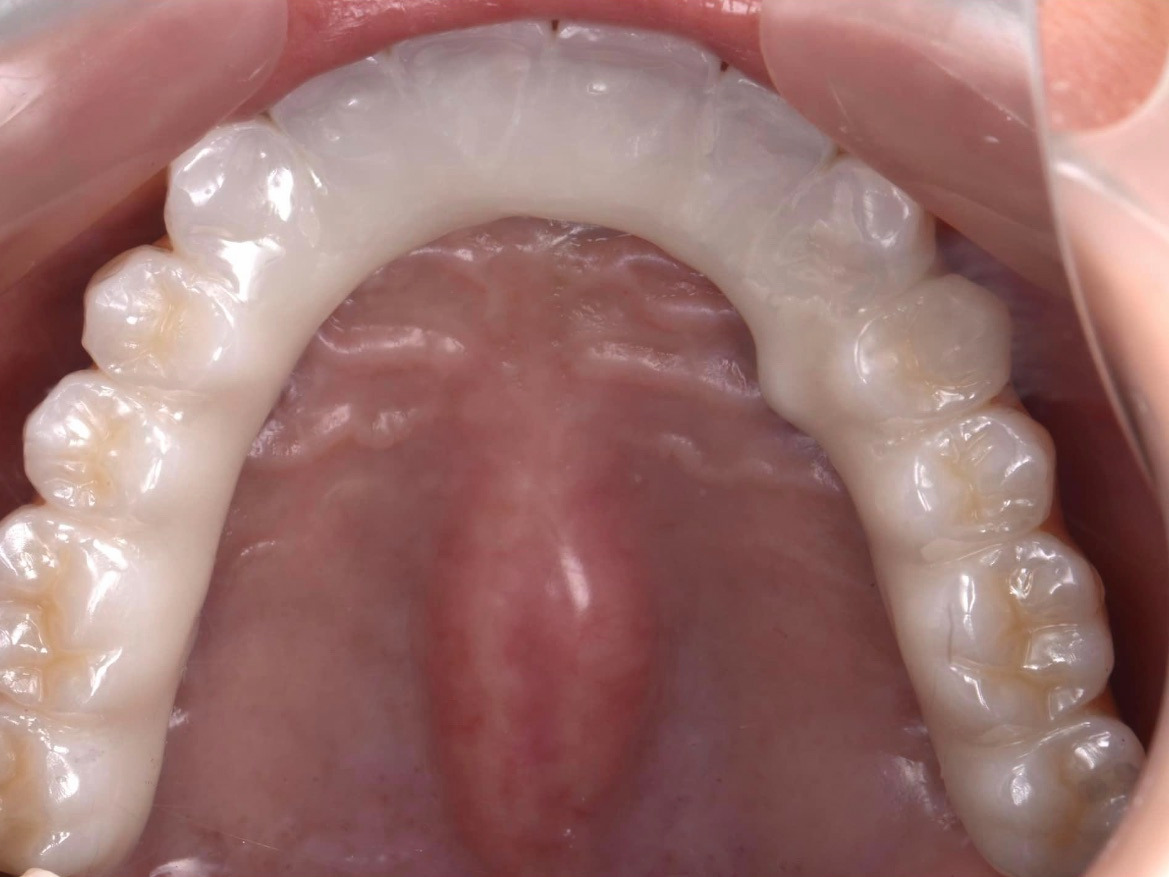

術前レントゲン、術後レントゲン。ジルコニアの単冠×4本の写真です。